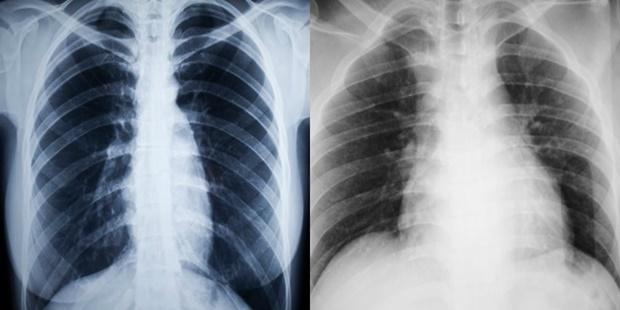

Εδώ βλέπετε την ακτινογραφία ενός ατόμου που δεν καπνίζει και έχει υγιείς πνεύμονες (αριστερά) και την αντίστοιχη ακτινογραφία ενός ατόμου που είναι χρόνιος καπνιστής και έχει κατεστραμμένους πνεύμονες (δεξιά).

Το κάπνισμα καταστρέφει τον πνευμονικό ιστό και αυτό είναι άμεσα ορατό στον καθένα. Ο καπνός από το τσιγάρο περιέχει περίπου 4.000 χημικές ουσίες, συμπεριλαμβανομένου του μονοξειδίου του άνθρακα. Αυτό δυσχεραίνει πολύ την λειτουργία των πνευμόνων και εμποδίζει το πολύτιμο οξυγόνο να κυκλοφορεί σωστά μέσα στο σώμα. Οι χημικές ουσίες στον καπνό του τσιγάρου ερεθίζουν και προκαλούν φλεγμονή στους αεραγωγούς και τους πνεύμονες.